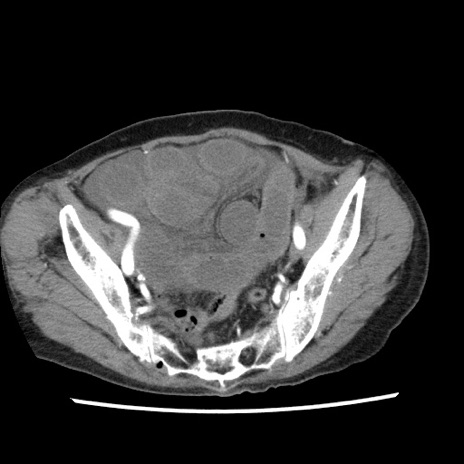

症例1(横断像)

【症例】80歳代女性

【主訴】腹痛

【現病歴】8時間前から腹痛あり来院。

【既往歴】糖尿病、脂質異常症、子宮体癌にて子宮全摘術

【身体所見】意識清明・会話良好だが腹痛で苦悶様、全腹部にわたって反跳痛と圧痛あり

【データ】WBC 13600、CRP 0.14、LDH 224、CK 90